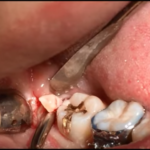

Estrazione dente del giudizio incluso: complicanze post-operatorie

Come risaputo, alcune condizioni di patologia a carico dei terzi molari inferiori in inclusione richiedono la risoluzione tramite avulsione degli stessi.